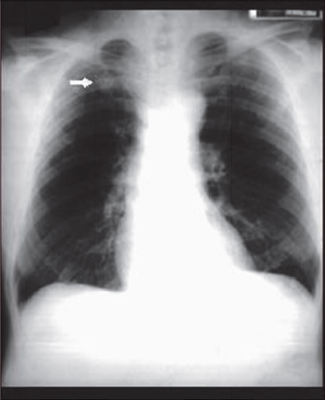

Question 10

Question

Revalida - 2013 Homem com 42 anos de idade, vendedor ambulante, foi admitido para emprego formal no comércio e procura a Unidade Básica de Saúde para saber como deve proceder com relação a uma alteração identificada nos exames admissionais, reproduzida na radiografia de tórax mostrada acima. À anamnese, refere tosse seca há mais de seis meses, constante, diária, nunca tratada. Nega febre, dispneia, hemoptise e perda de peso. Não apresenta outras queixas. É portador de hipertensão arterial, controlada com hidroclorotiazida. É fumante, com uma carga tabágica de 20 maços/ano, há 22 anos. Apresenta como antecedente familiar um irmão com tuberculose pulmonar tratada no ano passado. Nega outros antecedentes patológicos ou história familiar de doença. O exame físico é normal. A conduta mais apropriada para este paciente, neste momento, é:

Answer

• iniciar tratamento de prova para tuberculose.

• solicitar tomografia computadorizada.

• cessar tabagismo e observar.

• repetir radiografia do tórax.

• iniciar tratamento com macrolídeo.